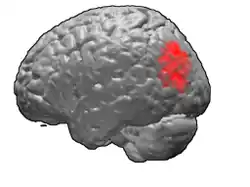

Brodmann area 39, or BA39, is part of the parietal cortex in the human brain. BA39 encompasses the angular gyrus, lying near to the junction of temporal, occipital and parietal lobes.

This area is also known as angular area 39 (H). It corresponds to the angular gyrus surrounding the caudal tip of the superior temporal sulcus. It is bounded dorsally approximately by the intraparietal sulcus. In terms of its cytoarchitecture, it is bounded rostrally by the supramarginal area 40 (H), dorsally and caudally by the peristriate area 19, and ventrally by the occipitotemporal area 37 (H) (Brodmann-1909).